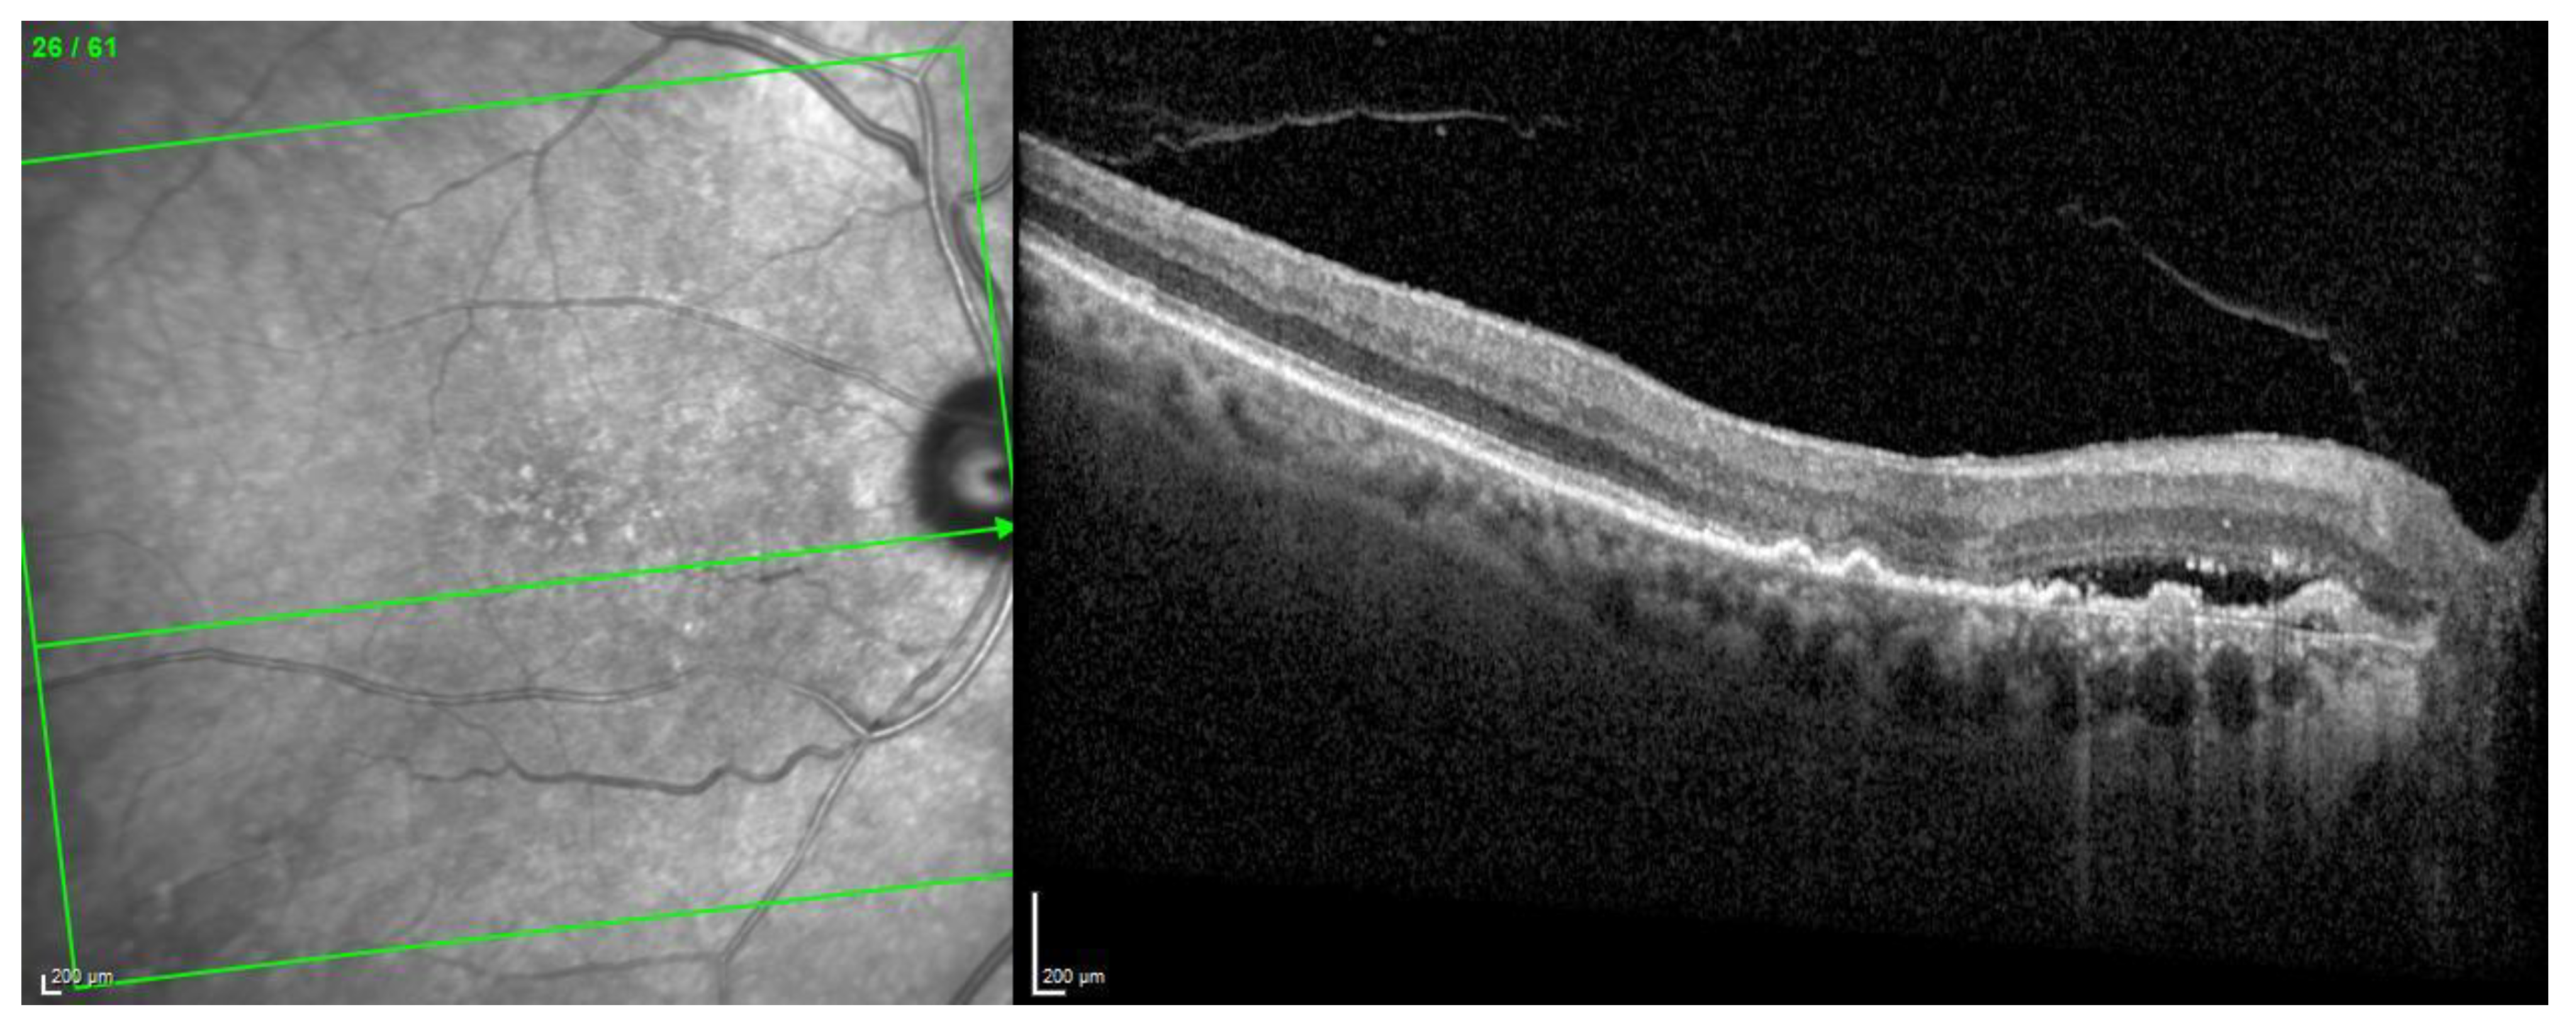

The OCT scan demonstrated a type 1 MNV with PED and BALAD in the right eye. The ceiling of the BALAD presented hyper-reflective foci. The EZ zone was attenuated at the floor (Figure 12).

Figure 12.

Case 7. Heidelberg Spectralis optical coherence tomography shows a peripapillary type 1 MNV with subretinal fluid and BALAD in the right eye.

The OCTA scan confirmed the presence of the right peripapillary MNV (Figure 13).

Figure 13.

Case 7. Heidelberg Spectralis optical coherence tomography angiography shows a peripapillary subretinal neovascular membrane in the right eye.

These features were shown to be partially responsive to the treatment. The BVCA was stable over the treatment period.